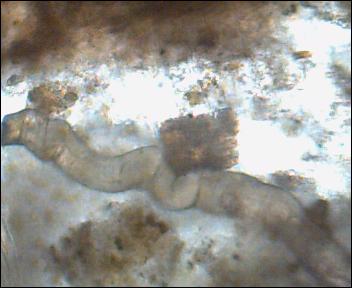

Był dziś u mnie kolega z Krakowa i przyniósł do sprawdzenia próbkę kupki do zbadania. Oto co znależliśmy.

Ta duża gruba glista to wg mnie może być człon tasiemca (wyrażnie widać oderwania). Były równiez wiciowce i 2 inne stworki. Co do stworków, to nie mam pewności co to jest.

- pow 200 x

poruszało sie dosć szybko - Obraz 006.jpg (22.34 KiB) Przejrzano 2794 razy

człon tasiemca? nie ruszało się to to - Obraz 001.jpg (16.9 KiB) Przejrzano 2794 razy